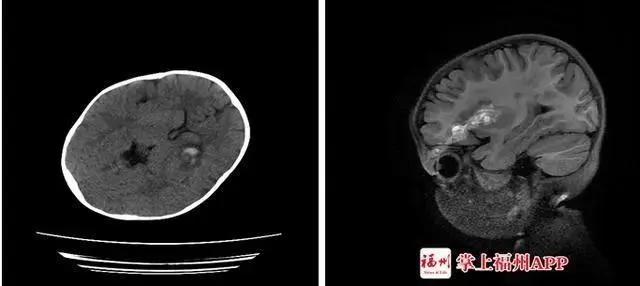

隨後,經過檢查醫生髮現,琳琳已經有了明顯的開放性顱腦損傷、顱內少量血腫、左眼眶上壁骨折,伴左眼眶周圍軟組織挫裂傷,「她出現玻璃體積血,後期視力可能受影響。」

孩子顱腦損傷。(圖/翻攝自掌上福州APP)